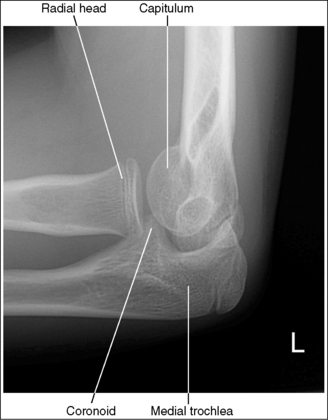

Contrast and density are adequate to demonstrate the anterior, posterior, and supinator fat pads, surrounding soft tissue, and bony structures.

• Fat pads on lateral elbow projection. To evaluate a lateral elbow projection, the reviewer not only analyzes the bony structure, but also studies the placement of the soft tissue fat pads. Three fat pads of interest are present on a lateral elbow projection, the anterior and posterior fat pads and the supinator fat stripe. The anterior fat pad should routinely be seen on all lateral elbow projections when adequate exposure factors are used. This pad is formed by the superimposed coronoid process and radial pads and is situated immediately anterior to the distal humerus (Figure 4-77). A change in the shape or placement of the anterior fat pad may indicate joint effusion and elbow injury. The posterior fat pad is normally obscured on a negative lateral elbow projection because of its location within the olecranon fossa. When an injury occurs, joint effusion pushes this pad out of the fossa, allowing it to be visualized proximal and posterior to the olecranon fossa. The supinator fat stripe is visible parallel to the anterior aspect of the proximal radius (see Figure 4-77). Displacement of this fat stripe is useful for diagnosing fractures of the radial head and neck.

The elbow is in a lateral projection. The distal humerus demonstrates three concentric arcs, which are formed by the trochlear sulcus, capitulum, and medial trochlea. The elbow joint space is open, and the radial head is superimposed over the coronoid process.

• A lateral elbow projection is obtained when the humeral epicondyles are positioned directly on top of each other, placing an imaginary line drawn between them perpendicular to the IR. To obtain this humeral epicondyle positioning, place the humerus parallel with the IR and elevate the distal forearm until the palpable medial and lateral epicondyles are superimposed (Figure 4-78). This positioning aligns the trochlear sulcus, capitulum, and medial trochlea into three concentric (having the same center) arcs (Figure 4-79). The trochlear sulcus is the small center arc. It moves very little when a positional change is made and works like a pivoting point between the capitulum and medial aspect of the trochlea. The largest of the arcs is the medial aspect of the trochlea. It is demonstrated very close to and slightly superimposed on the curve of the trochlear notch. The intermediate-sized arc is the capitulum. When these three arcs are in accurate alignment, the elbow joint is visualized as an open space and the anterior and proximal surfaces of the radial head and coronoid process are aligned.